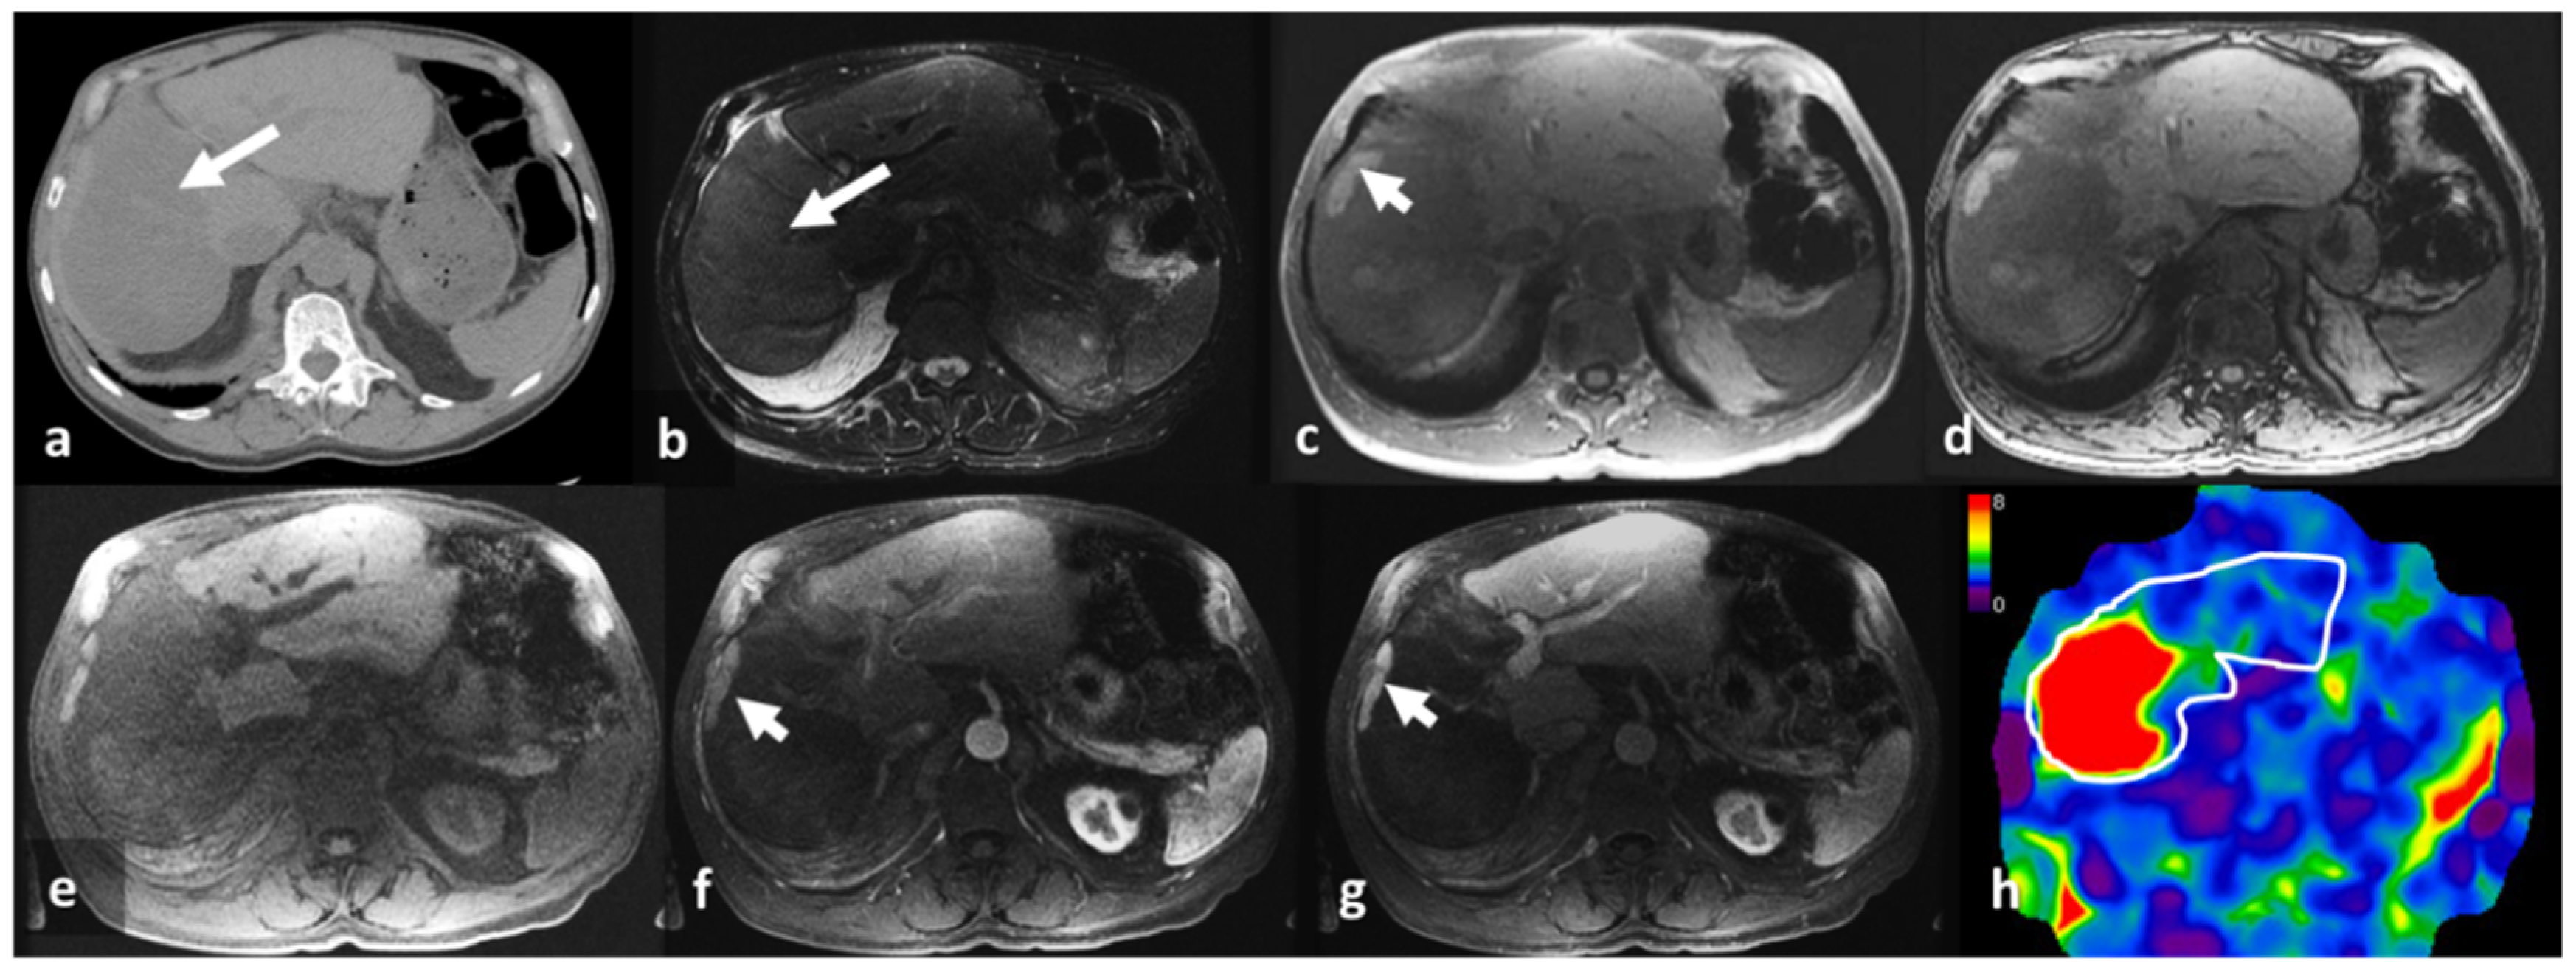

- Srinivasan, S.; Tan, Y.Q.; Teh, H.S.; Lee, P.J.; Khoo, R.N. Primary hepatic amyloidosis presenting as nodular masses on the background of diffuse infiltration and extreme liver stiffness on MR elastography. J. Gastrointestin. Liver Dis. 2014, 23, 437–440. [Google Scholar]

- Trifanov, D.S.; Dhyani, M.; Bledsoe, J.R.; Misdraji, J.; Bhan, A.K.; Chung, R.T.; Samir, A.E. Amyloidosis of the liver on shear wave elastography: Case report and review of literature. Abdom. Imaging 2015, 40, 3078–3083. [Google Scholar] [CrossRef] [PubMed]

- Matsuda, S.; Motosugi, U.; Kato, R.; Muraoka, M.; Suzuki, Y.; Sato, M.; Shindo, K.; Nakayama, Y.; Inoue, T.; Maekawa, S.; et al. Hepatic Amyloidosis with an Extremely High Stiffness Value on Magnetic Resonance Elastography. Magn. Reson. Med. Sci. 2016, 15, 251–252. [Google Scholar] [CrossRef]

- Wells, M.L.; Fenstad, E.R.; Poterucha, J.T.; Hough, D.M.; Young, P.M.; Araoz, P.A.; Ehman, R.L.; Venkatesh, S.K. Imaging Findings of Congestive Hepatopathy. Radiographics 2016, 36, 1024–1037. [Google Scholar] [CrossRef] [PubMed]